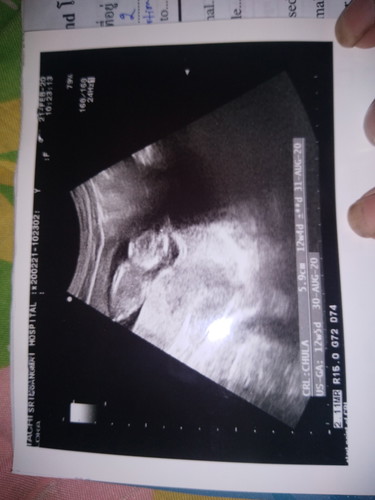

วันนี้ไปซาวด์มาค่ะ

อยากทราบว่าลูกตัวเล็กมากค่ะต้องกินอะไรจะตัวใหญ่ค่ะเเต่เเม่ก้กินตลอดค่ะไม่หยุดปากเลยนมกล้วยข้าวก้กินค้ะ

คุณหมอบอกเหรอค่ะว่เด็กตัวเล็ก ดูในใบซาวด์อายุครรภ์ก็เกือบจะเท่าอายุครรภ์จริงนี่ค่ะ ต่างกันวันเดียว